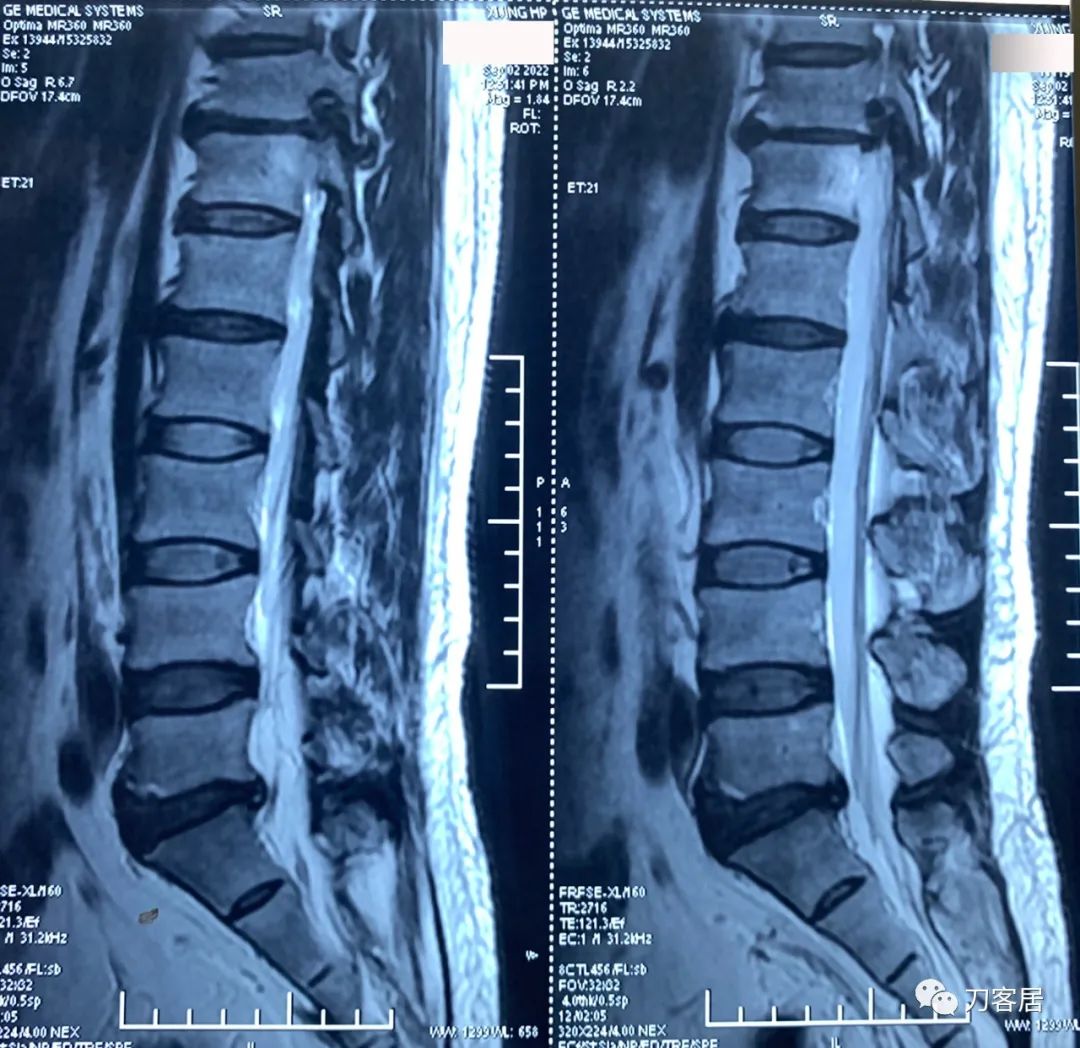

图23. 20220902西京医院腰椎MRI01,显示腰5骶1椎间盘突出,但不严重。

图24. 20220902西京医院腰椎MRI02,显示腰5骶1椎间盘突出,但不严重。

图25. 20220902西京医院腰椎MRI报告